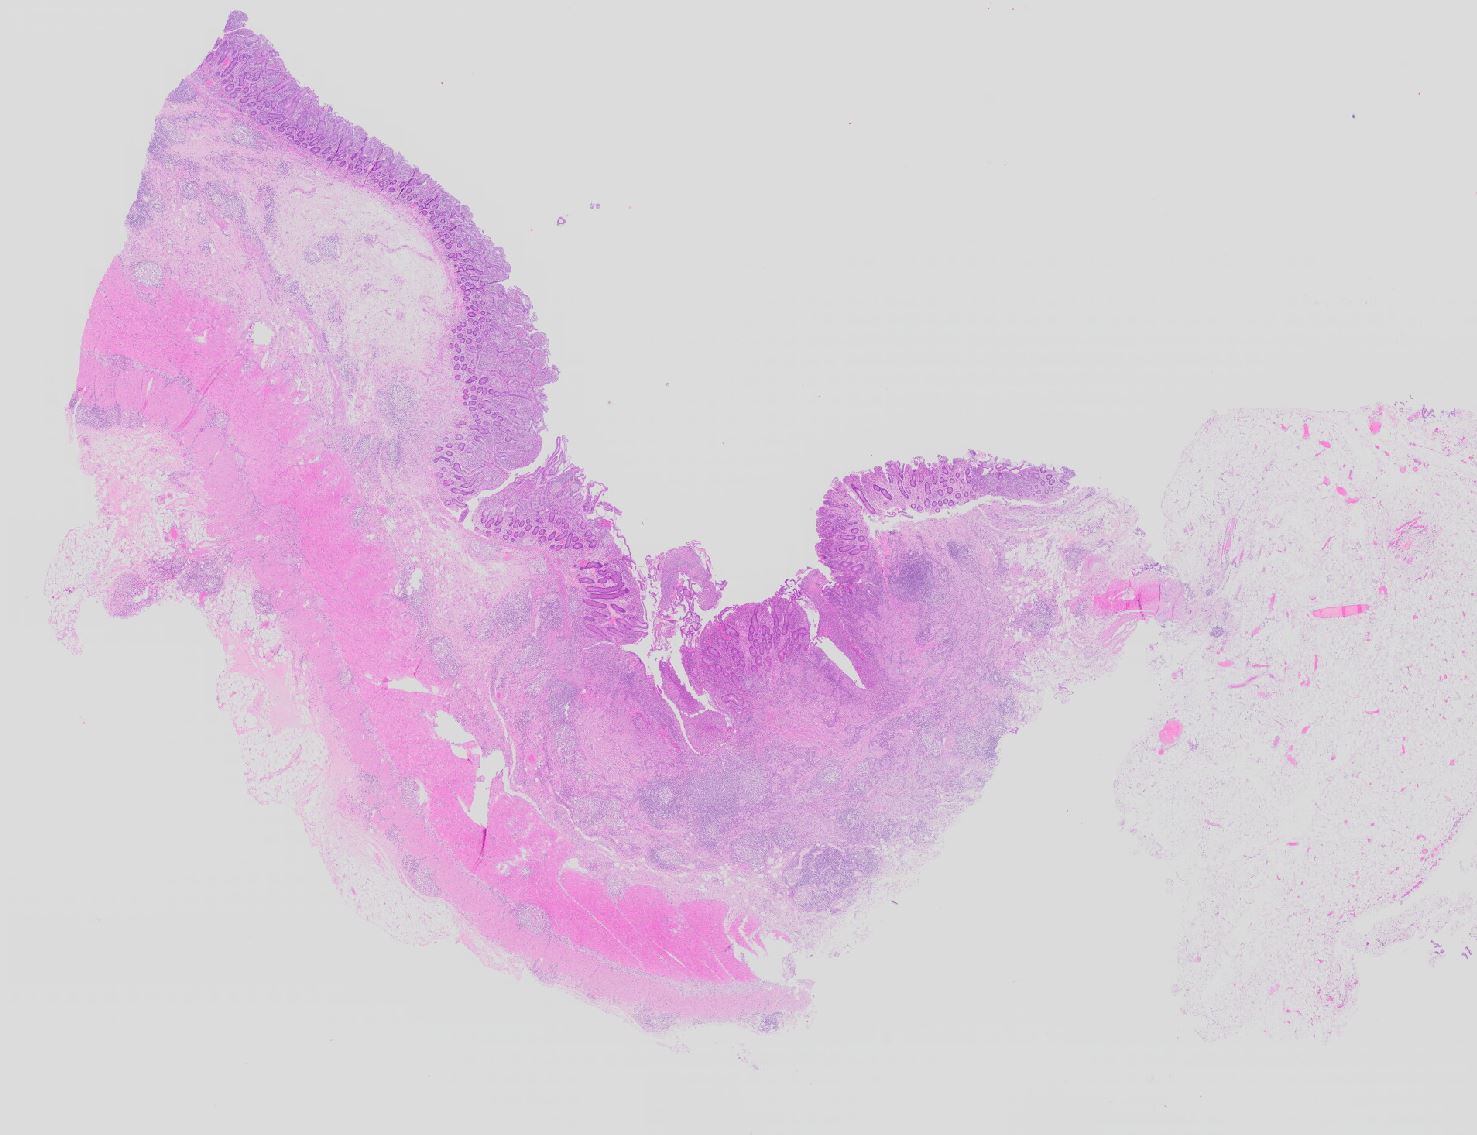

PathoPic – image database / PathoPic ID 11375 - Morbus Crohn

Morbus Crohn

Systemerkrankung/Immunpathologie

Ileum terminal

Darm, Anus

Morbus Crohn des Dünndarms. Status nach Hemikolektomie rechts. Parailealer Abszess. Ileokoloische Resektion.

Histologie